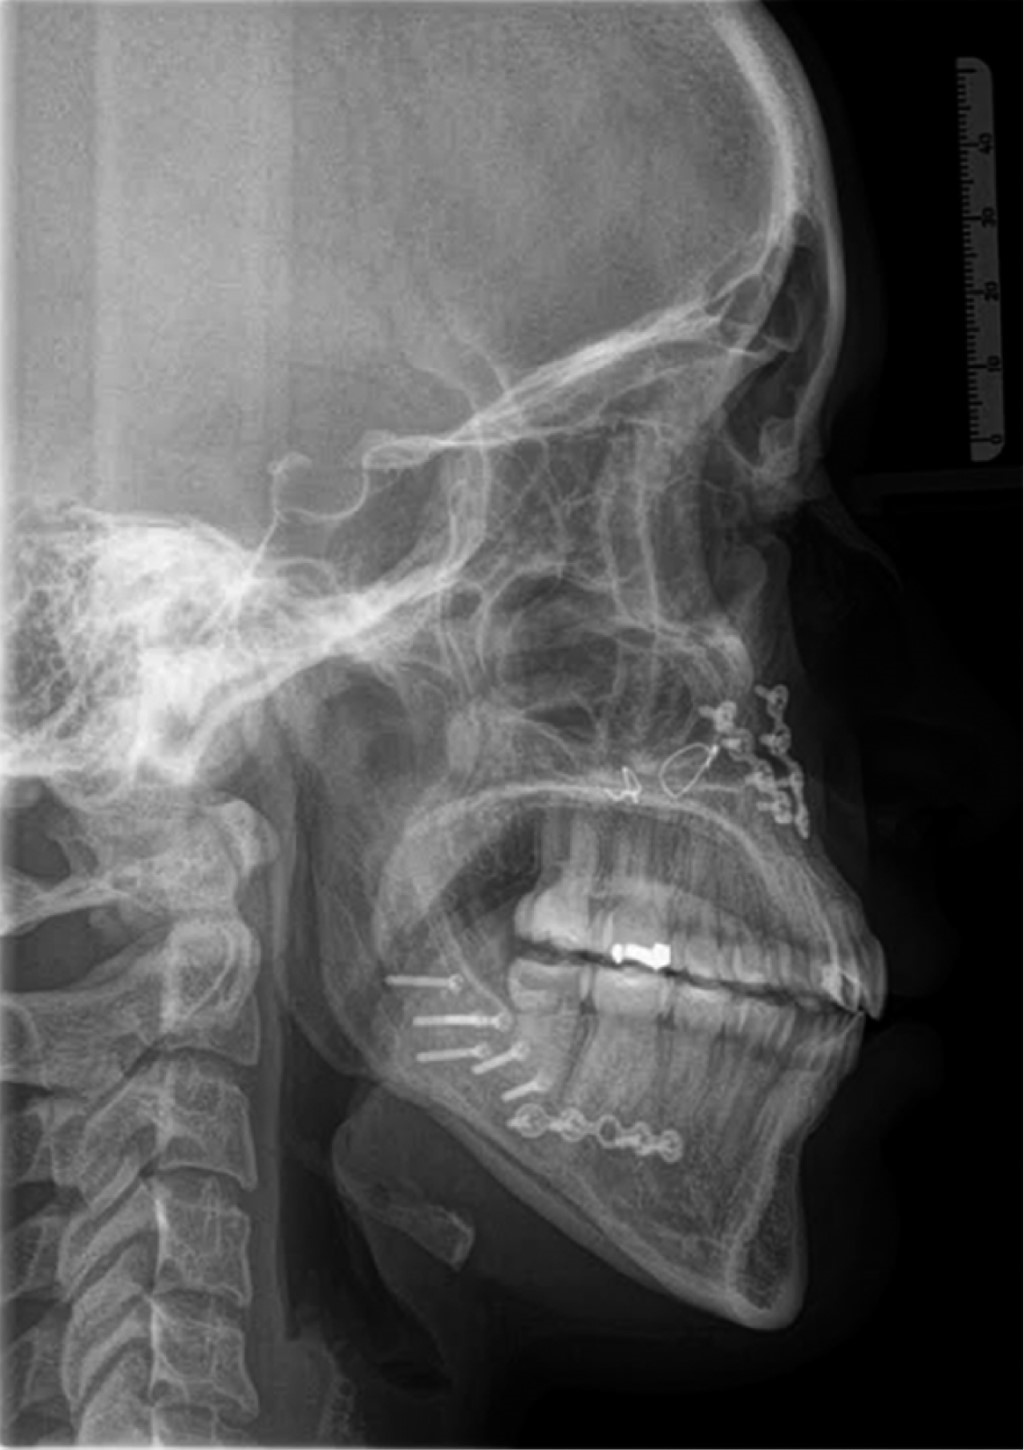

De acuerdo con la evaluación de los estudios radiográficos (Figuras 3 y 4), fotografías extra- e intraorales y datos cefalométricos (Tabla 1) se decide realizar tratamiento ortodóncico-quirúrgico y de esta manera cumplir con los objetivos planeados.

Al cabo de 18 meses se revaloró el caso con estudios radiográficos y modelos de estudio junto con el Departamento de Cirugía Oral y Maxilofacial y se programó la cirugía ortognática. Se colocaron arcos quirúrgicos previos a la cirugía, arco 0.019" × 0.025" de acero inoxidable con ganchos quirúrgicos. La primera fase del tratamiento constó de 20 meses.

La duración del tratamiento fue de 32 meses, se alcanzó la coordinación de ambas arcadas, se corrigió el exceso de crecimiento vertical de la paciente, se consiguió clase I canina bilateral, sonrisa con arco positivo, correcta guía anterior (overjet y overbite), coincidencia de las líneas medias, se eliminó la mordida borde a borde en sector anterior y la mordida cruzada en sector posterior derecho (Figuras 5 y 6). En el examen radiográfico se observó paralelismo radicular y las adecuadas inclinaciones de los incisivos (Figuras 7 y 8, Tabla 2).

Figura 3

Figura 4